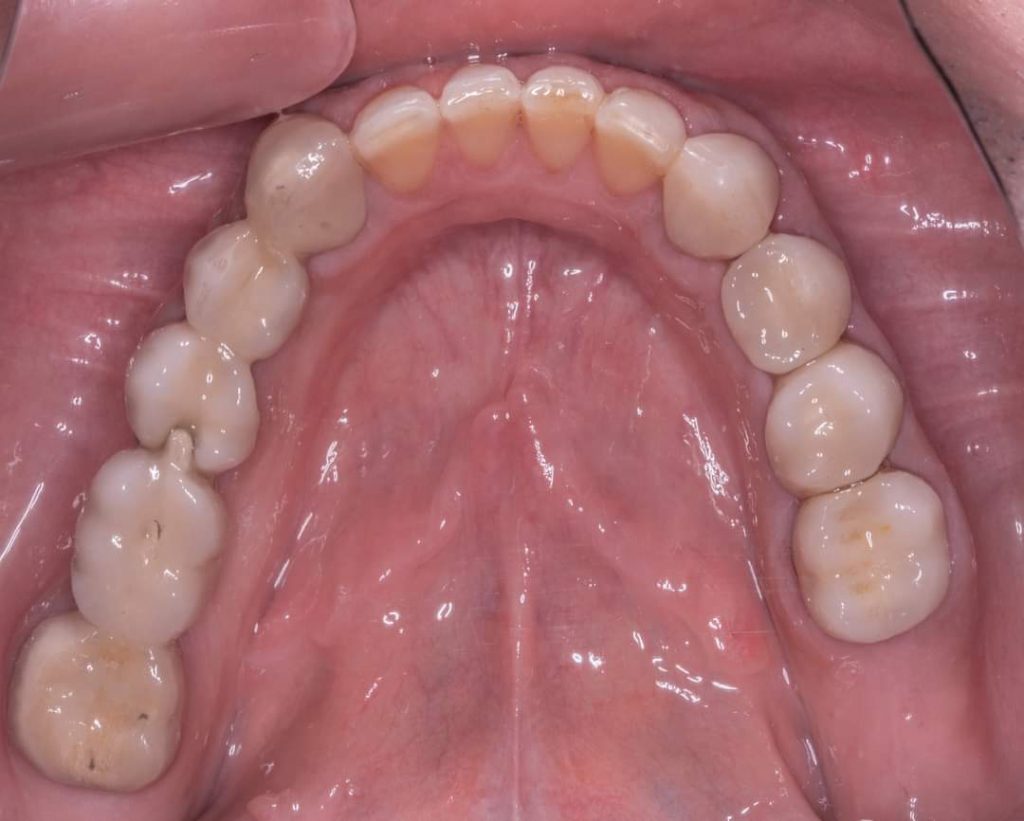

Impressions were done also, Wax Bite registration then pouring casts for wax up

PFM crowns on 13,12,11,21,22,23,33,34,35,36

Metallic RPD done on surveyed crowns no.13,17… 23,27

Aker claps on 17,27

Cingulum rest seat and RPI clasp on surveyed crowns